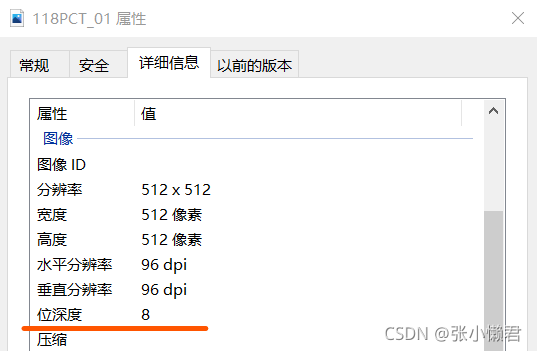

#imageio.imsave()函数将从DICOM文件中读取到的512*512的矩阵转换成--->单通道的灰度图像(512,512)

imageio.imsave("118PCT_01.JPG", img_arr)